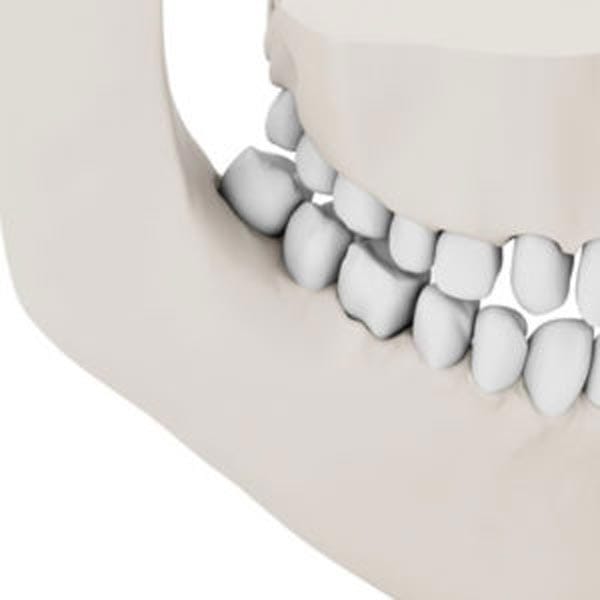

Implants and Bone Loss

A tooth’s root is important to help maintain bone health. When the root is missing or removed, such as when a tooth is extracted, the bone in that area is reabsorbed by the body and can cause a number of oral issues. Dental implants take the place of the missing root, stimulating the jawbone, and preventing this deterioration.

The bone loss progression models pictured here shows, in the left image, a normal complement of teeth and natural lower jaw bone mass and height.

Dr. Nazarian uses specialized bone grafting products and implant placement procedures to replace lost bone and to provide sensible anchoring methods for patients who prefer removable prosthetics.

For those patients who have been told they are not a candidate for traditional dental implant treatments, Dr. Nazarian can use subperiosteal devices to recreate an entire ridge of new bone that’s necessary for attaching prosthetic teeth.